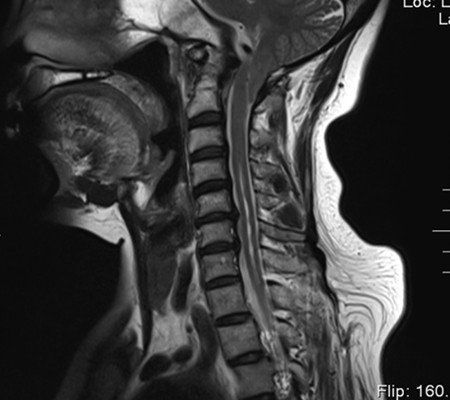

患者,女,53歲,以“頸肩部麻木、疼痛10月”入住神經(jīng)外科一病區(qū)。該患者小腦扁桃體下疝畸形,頸椎先天發(fā)育也有異常。

主任劉增強(qiáng)、責(zé)任總醫(yī)師巨濤等人就此病例進(jìn)行了多次討論。術(shù)前第一次運(yùn)用先進(jìn)的3D打印技術(shù)重塑了患者的寰枕部骨質(zhì)及血管,證實(shí)了患者先天性寰椎后弓缺如。經(jīng)過充分的術(shù)前準(zhǔn)備,顯微鏡下切除了下疝的小腦扁桃體,結(jié)合3D打印結(jié)果,歷時4小時完成了我院第一例后路減壓+枕頸內(nèi)固定術(shù)?;颊咝g(shù)后3天下床活動,10天出院。

寰枕畸形是指枕骨底部及第一、二頸椎先天發(fā)育異常,除以骨骼為主的發(fā)育異常外,還合并有神經(jīng)系統(tǒng)和軟組織發(fā)育異常,包括扁平顱底、顱底陷入、寰枕融合、頸椎分節(jié)不全、寰樞椎脫位、小腦扁桃體下疝畸形等。